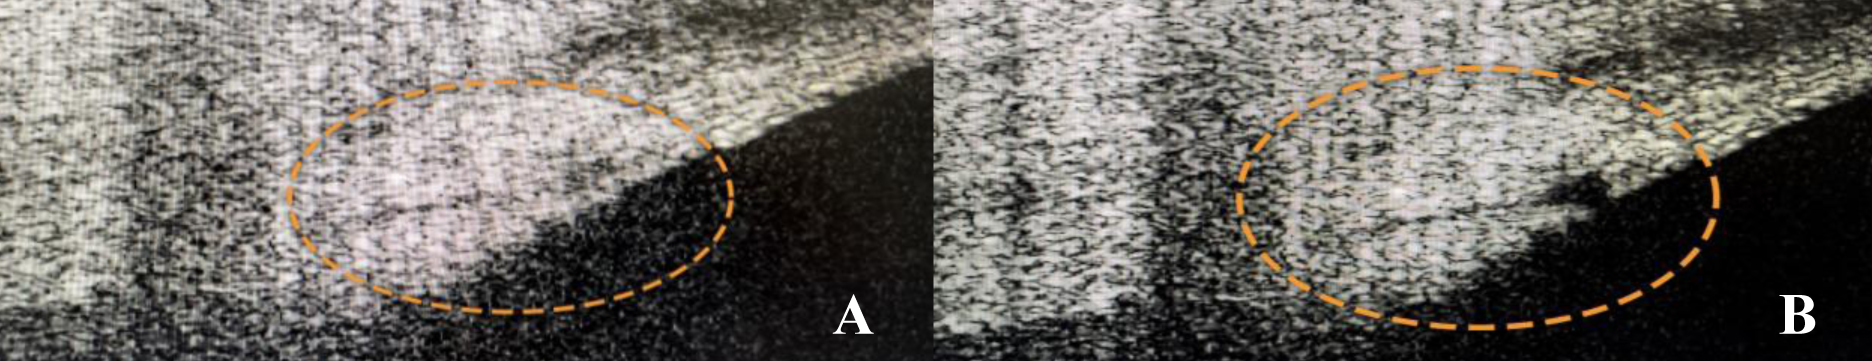

На рис. 1 представлено состояние трабекулы и коллекторных канальцев до и после комбинированной технологии оптимизированной YAG-лазерной трабекулостомии. Исходно: большая ось Шлеммова канала – 220 мкм, малая ось – 38 мкм, площадь среза Шлеммова канала: 6 563 мкм2. После операции: большая ось Шлеммова канала – 275 мкм, малая ось – 51 мкм, площадь среза Шлеммова канала: 11 010 мкм2 .

Рис. 1. ОКТ трабекулы и коллекторного канальца до (А) и после (B) комбинированной технологии YAG-лазерной трабекулостомии